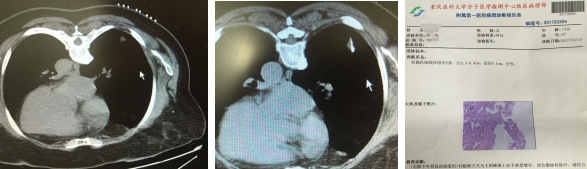

患者xxx,女,71岁,重庆潼南人,院外体检发现右下肺5*5mm大小的孤立结节影。辗转多家医院来我院呼吸科就诊,以求明确诊断。呼吸科李长毅副主任为首的治疗小组,于2017年5月9日,在CT引导下成功精准穿刺活检,最后病理考虑原位腺癌可能,已经转胸外科手术治疗。患者非常幸运,在原位癌极早期明确诊断,并手术切除,可以达到治愈的效果。

呼吸内科作为国家临床重点专科,在近两年积极面对肺部微小结节多发的严峻形式。创新开展肺部微小结节的精准穿刺活检术,取得长足进步。1cm以下肺部微小结节已经作为常规穿刺(国内有报道的穿刺微小结节最小3.2mm,我科最小结节4mm),成功诊断多起早癌、甚至原位癌。在业界获得强烈的反响,充分体现了国家临床重点专科水平。